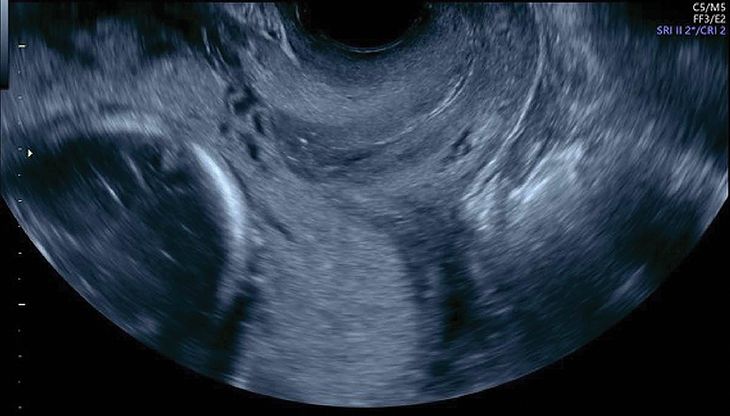

Transvaginal Ultrasound In Placenta Previa

Transvaginal sonogram of a complete placenta previa (PP). Note ...

A) Transvaginal ultrasound: presentation of a placenta previa ...